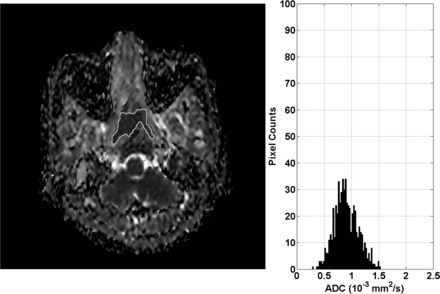

ADC map and histogram of primary NPC before treatment in a 50-year-old woman with local failure. The histogram shows that the greatest frequency of ADC values is shifted toward the central ADC range (ADC skewness = 0.11) and the peak is broadened (ADC kurtosis = 3.89).

DWI and Tumor Volume

The pretreatment ADC mean, ADC skewness, ADC kurtosis, primary tumor volume, T-stage, and patient age for the group of patients with LF and the group of patients with LC and the statistical analysis are shown in Table 1. Comparison of these 2 groups showed a statistically significantly lower ADC skewness (ADC values with the greatest frequencies were shifted away from the lower ADC range) and ADC kurtosis (ADC curve peak broader) in the group with LF (Fig 1) compared with the group with LC (Fig 2) (P = .006 and .024, respectively). There was a trend toward higher tumor volumes in the group with LF, but the difference was not significant (P = .256). The other parameters also showed no significant differences. ADC skewness and kurtosis significantly predicted LF in univariate analysis, but only ADC skewness remained significant (P = .044) in multivariate analysis. Side-by-side boxplots of the ADC skewness values of tumors with LF and LC are shown in Fig 3. Moreover, a threshold of ADC skewness of ≤0.55 (P = .0001) was identified as a predictor of LF in ROC curve analysis (Fig 4); the diagnostic performance of ADC skewness is shown in Table 2.